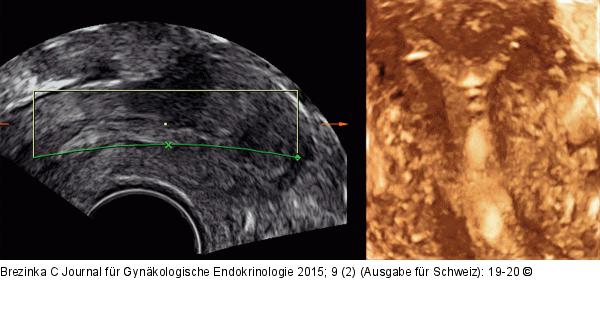

Abbildung 4: Ultraschall-Hormonspirale 3D-Ultraschall einer Jaydess® bei leichtem Uterus arcuatus. Der Hormonzylinder ist nicht orthograd getroffen, allerdings sind der Silberring und die Spitzen der beiden Seitenärmchen gut zu erkennen. |

3D-Ultraschall einer Jaydess® bei leichtem Uterus arcuatus. Der Hormonzylinder ist nicht orthograd getroffen, allerdings sind der Silberring und die Spitzen der beiden Seitenärmchen gut zu erkennen. |